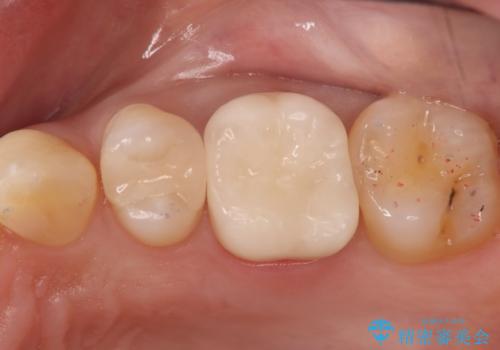

- 左上6番の奥歯のコンタクト下カリエス(歯と歯の間の虫歯)を主訴にご来院されました。レントゲンと精密診査の結果、歯と歯の間という、再発しやすい部位の虫歯であることが判明。患者様のご希望と口腔内の状態を考慮し、虫歯を徹底的に除去し、精密で再発リスクの低いセラミッククラウンで修復する治療計画を立案しました。これにより、見た目の美しさだけでなく、長期的な歯の健康維持を目指します。

治療では、まず虫歯に侵された歯質を丁寧に除去し、セラミッククラウンを装着するための歯の形成を行いました。型取りから患者様の歯の形や色に合わせたオーダーメイドのセラミッククラウンを作製。セラミックは、隣接する歯との隙間なく精密に適合し、プラークが付着しにくいため、虫歯の再発を防ぐ効果があります。最終的に、精度の高いクラウンを装着し、咬み合わせを細かく調整しました。これにより、虫歯の再発を防ぎ、快適に食事ができる奥歯を取り戻していただけました。